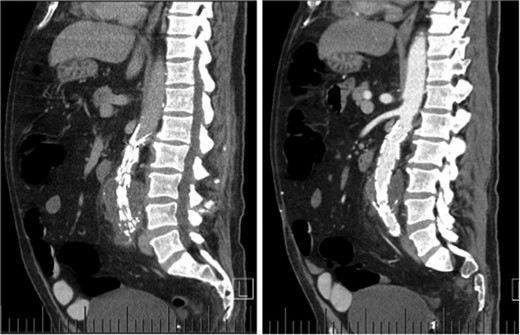

Computed tomography (CT) angiography revealed increased aortic size compared with a scan 1-month prior (5.4 cm compared with 5.0 cm) with diffuse peri-aortic inflammation. The findings implied an infected endograft (Figs 1 and 2).

Coronal CT images indicating enlarged aneurysm sac (left) and para-aortic fat stranding (right) representing periaortitis.